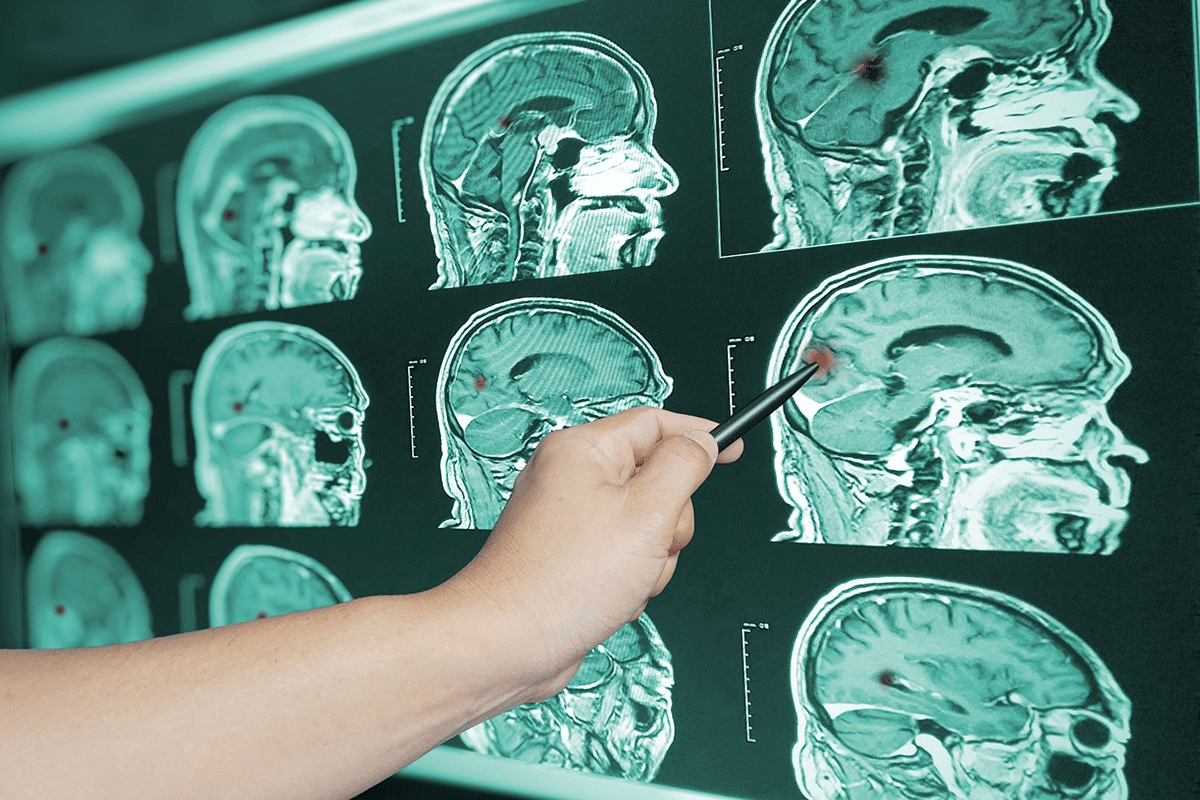

Imaging Techniques for Detection

Imaging is key in diagnosing Alzheimer’s. Positron Emission Tomography (PET) scans and Magnetic Resonance Imaging (MRI) are used often. PET scans spot amyloid plaques and tau tangles. MRI shows brain structure and atrophy.

A study in the Journal of Alzheimer’s Disease found PET imaging improves diagnosis. It helps track disease progression.

“PET imaging has emerged as a valuable tool in the diagnosis and monitoring of Alzheimer’s disease, providing insights into the underlying pathology.”

Nature Reviews Neurology